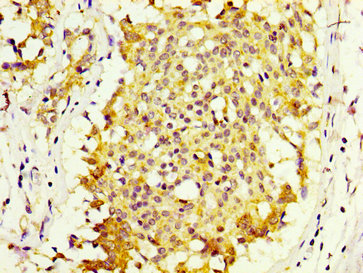

IHC image of PACO56202 diluted at 1:600 and staining in paraffin-embedded human breast cancer performed on a Leica BondTM system. After dewaxing and hydration, antigen retrieval was mediated by high pressure in a citrate buffer (pH 6.0). Section was blocked with 10% normal goat serum 30min at RT. Then primary antibody (1% BSA) was incubated at 4°C overnight. The primary is detected by a biotinylated secondary antibody and visualized using an HRP conjugated SP system.